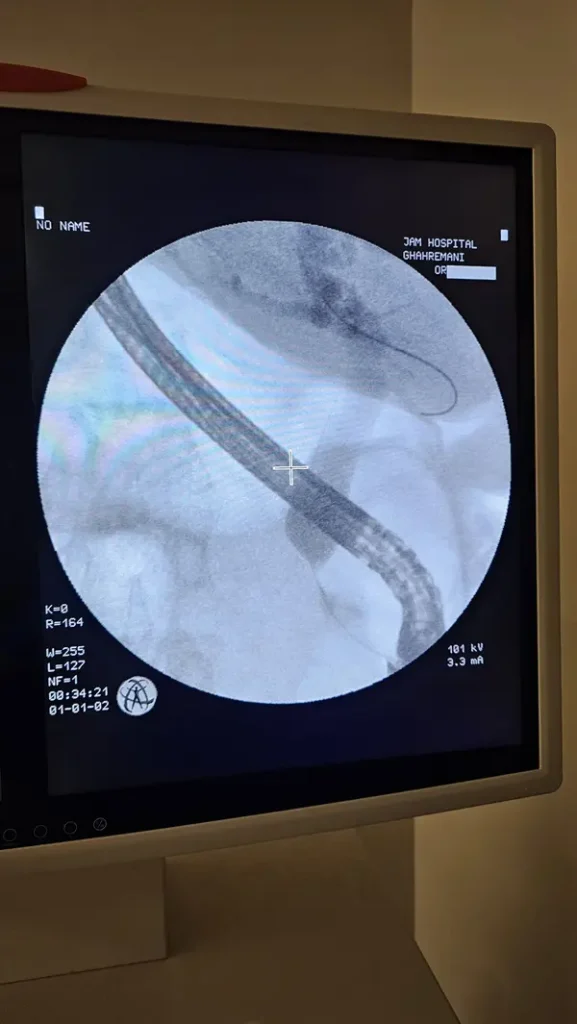

درباره ERCP بیشتر بدانیم

ERCP یک نوع تصویر برداری است که همانند آندوسکوپی از طریق دهان لوله ای وارد می شود. و از مجموعه صفراوی و پانکراست تصویربرداری انجام می شود.

در ادامه تصاویر و فیلم ERCP آقای ۶۶ ساله دارای سرطان سر پانکراس که غیر قابل عمل بود را مشاهده مینمایید.

ای آر سی پی در تشخیص سنگ های صفراوی، زخم ها، سرطان ها، تومورها و ضایعات احتمالی در لوزالعمده و پانکراست کاربرد دارد.

با استفاده از ERCP زردی و یرقان که در اثر انسداد مجاری صفراوی به وجود می آید را می توان درمان نمود.

همچنین بالن های خروجی سنگ های صفراوی با استفاده از ای ار سی پی انجام می شود.

مزیت ای آر سی پی در جلوگیری از جراحی های باز است.

نمونه هایی از عمل جراحی ERCP توسط دکتر رضادوست